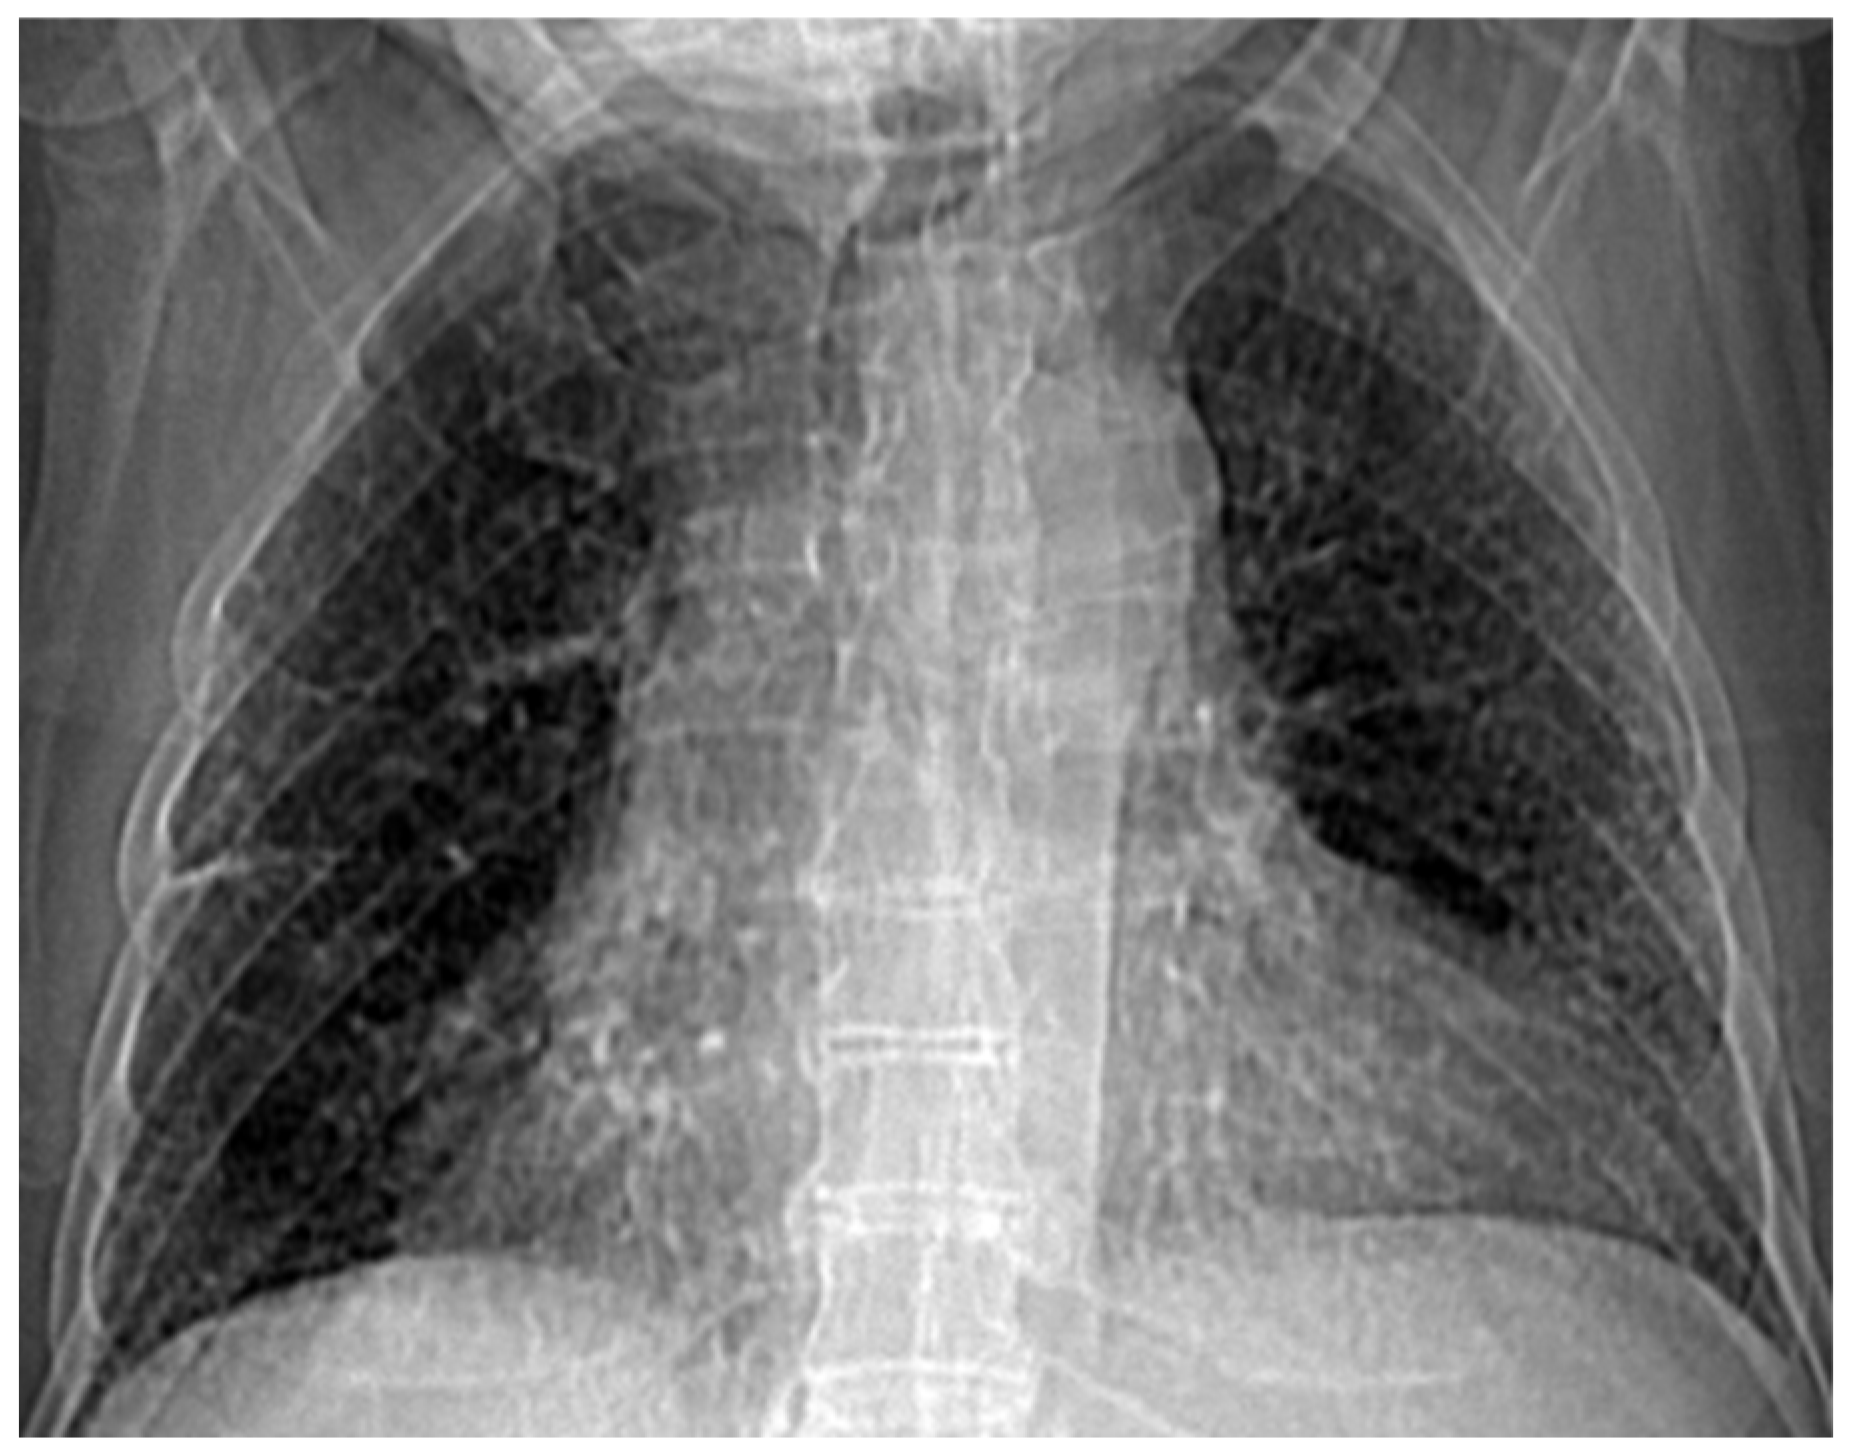

Figure 2 and Figure 3 show the selection of the lung portion of interest for patient MT and the same image in “Invert color” format.

Figure 2. The selection of the portion of interest of the lungs of patient MT.

Fractalfract 07 00285 g002

Figure 3. The image from Figure 2 in “Invert color” format.

Fractalfract 07 00285 g003